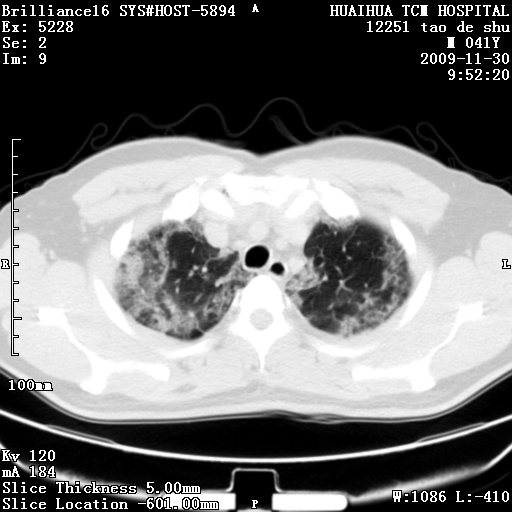

男性,41岁,林业局干部。5天前(2009-11-25)因受寒咳嗽发热在市一医院门诊就诊,胸片报告支管炎。门诊治疗无好转,遂转入我院住院治疗。现主要为发热,38度,咳嗽较轻。血象不高,中性72%,嗜酸性细胞未见报告。血小板8万。尿有蛋白管型。肝功能异常。心电图:阵发性心动过速。请分析ct是什么病。

补充图片:

肺窗图像太少,考虑间质性肺炎

两肺上叶炎性改变,查一下咽拭子培养考虑甲流?

两肺外带斑片状及磨玻璃样高密度灶,考虑感染性病变,过敏性肺炎不除外。

1、双肺感染性病变,查有无重症甲流

2、查过 hiv,不能除外pcp